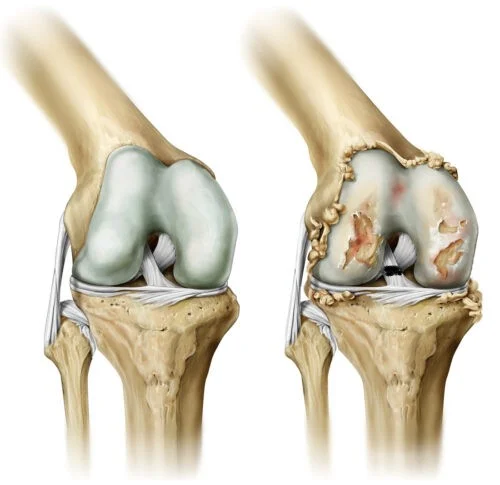

كل ما تحتاج لمعرفته عن القطع الجزئي في الرباط الصليبي؛ هذا ما سنقوم بتوضيحه خلال السطور القادمة تحت اشراف الدكتور ياسر رضا؛ وهذا ما يبحثه عنه عدد كبير من الأشخاص الذين يعانون من القطع الجزئي؛ حيث يعتبرالرباط الصليبي الأمامي عبارة عن هيكل قوي يتكون من أنسجة ضامة ويقع في وسط الركبة، حيث يلعب دورًا أساسيًا في استقرار المفصل ويعزز التحكم في حركة الساق؛ كما يعد الرباط الصليبي الأمامي والخلفي الأكثر أهمية، حيث يحد من الحركة المفرطة ويمنع انزلاق عظمة الفخذ على الساق؛ كما يساهم هذا الرباط في الحفاظ على التوازن والقدرة على أداء الحركات بشكل سليم؛ ويعتبر تمزق جزئي في الرباط الصليبي يعني حدوث تمزق غير كامل في الرباط، مما يؤثر جزئيًا على استقرار ووظيفة الركبة؛ كما يمكن اعتباره حالة متوسطة بين الإصابات البسيطة مثل التواء الرباط، والتمزق الكامل الذي يؤدي إلى فقدان كامل لوظيفة الركبة؛ ويختلف التمزق الجزئي عن التمزق الكامل من حيث شدة الإصابة وتأثيرها على أداء الشخص، حيث يكون التمزق الكامل غالبًا مصحوبًا بأعراض أكثر شدة، مثل ألم شديد وصعوبة في القدرة على تحميل الوزن.

فيما يتعلق بعلاج تمزق جزئي في الرباط الصليبي، تتنوع الخيارات بين العلاج غير الجراحي والجراحة< حيث في الحالات البسيطة، يميل الأطباء إلى اتباع العلاج المحافظ، الذي يشمل فترة من الراحة، واستخدام الثلج، والعلاج الطبيعي لتحسين قدرة المريض على الحركة وتقوية العضلات المحيطة بالركبة؛ بينما في الحالات الأكثر خطورة، قد تكون الجراحة ضرورية لإصلاح الرباط؛ وتتفاوت فترة العلاج وفقا لشدة الإصابة، حيث يمكن أن تتراوح مدة التعافي من عدة أسابيع إلى عدة أشهر من المهم أيضًا التنويه إلى أن الرباط الصليبي لا يتجدد بشكل طبيعي بعد التمزق الجزئي، مما يبرز أهمية اتخاذ الإجراءات المناسبة للحفاظ على صحة الركبة وأدائها.